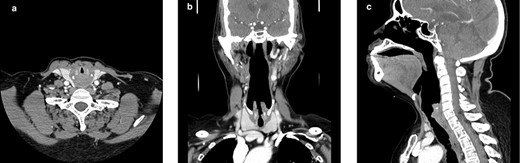

Inflammatory markers were reassuring (white cell count 9.17 and C-reactive protein 17) and an initial chest X-ray showed an improving reticulonodular pattern compared with previously. A swab was negative for COVID-19. A computerized tomography (CT) scan of the neck revealed thickening and oedema from the supraglottic region down to the subglottic region (Fig. 1). The narrowing at the subglottic region was ~4.6 mm on CT compared with a pre-COVID-19 diameter of 10.3 mm on CT. At the narrowest point, there was an approximate cross-sectional obstruction of 80%, which would be consistent with a grade 3 obstruction according to the Cotton–Myer classification [7]. Flexible nasendoscopy (FNE) confirmed a circumferential subglottic stenosis.

Computerized tomography images of the neck showing stenosis, worst at the subglottic level; (a) axial plane; (b) coronal plane; (c) sagittal plane.